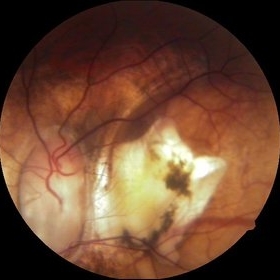

Choroidal Rupture

Sep 12 2014 by Mehul A Shah

A 24-year-old boy presented with history of cricket ball injury.

Photographer: Drashti Netralaya,Dahod

Imaging device: Zeiss ff450

Condition/keywords: choroidal rupture